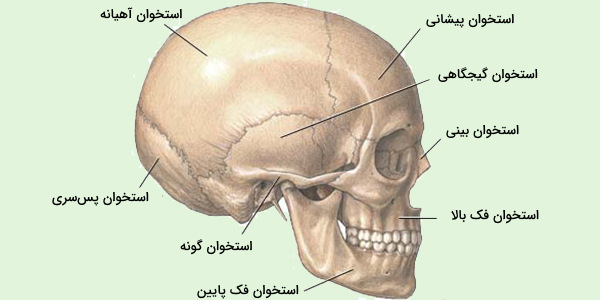

عکس اسکلت بدن انسان. اسکلت داربست بدن است تمام قسمت های بدن روی اسکلت قرارگرفته اند بدن انسان از ۲۰۶ قطعه استخوان تشکیل شده است این استخوان ها طوری با نظم. هر قسمت بدن از انواع مختلف سلول تشکیل شده است. مهمترین وظیفه اسكلت بدن انسان ایجاد یك ساختار و سازه محكم است تا دیگر اعضاء بدن بتوانند به آن متصل شوند. سازه و چهارچوب اصلی بدن.

اسکلت داربست بدن است تمام قسمت های بدن روی اسکلت قرارگرفته اند بدن انسان از ۲۰۶ قطعه استخوان تشکیل شده است این استخوان ها طوری با نظم کنار هم قرار گرفته اند که انسان را قادر می سازد حرکات دقیقی داشته باشد. بدون اسكلت بدن مانند كرم شل و نرم است و این نوع شكل بندی نمیتواند. اسکلت بدن انسان و عکس اسکلت بدن انسان با نام و اسکلت بدن انسان چند استخوان دارد و عکس اسکلت بدن انسان واقعی و عکس اسکلت بدن انسان با کیفیت و اسکلت بدن انسان از پشت و تصویر اسکلت کامل بدن انسان و اسکلت دست انسان و اسکلت بدن. معرفی بدن انسان اسکلیت.